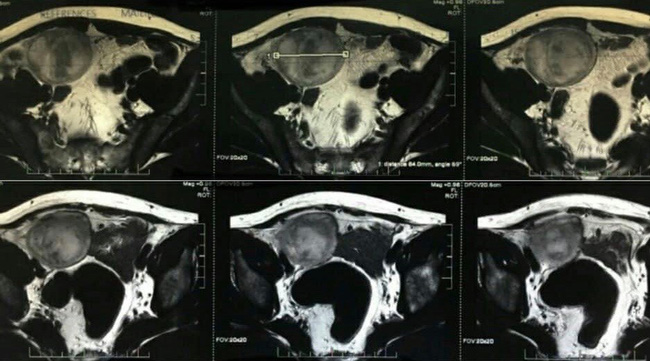

Bệnh nhân N.X.K, 44 tuổi, ở Phú Thọ, đã có vợ và 3 con. Ngay từ nhỏ, bệnh nhân không thấy tinh hoàn phải trong bìu. Khoảng 1 năm nay xuất hiện khối đau tức ở hố chậu phải. Anh K đến Bệnh viện Hữu nghị Việt Đức khám. Phim chụp cộng hưởng từ có khối u ở hố chậu phải, kích thước khoảng 7cm, nghĩ tới u tinh hoàn bên phải. Ngày 10/8, các bác sĩ đã tiến hành phẫu thuật nội soi cắt toàn bộ khối u tinh hoàn bên phải trong ổ bụng.

Trước đó, các bác sĩ Trung tâm Nam học cũng phẫu thuật nội soi cắt toàn bộ u tinh hoàn trái trong ổ bụng cho bệnh nhân N.H.L, 37 tuổi, là giáo viên, đã có vợ và hai con. Anh L không điều trị ở đâu, đến viện trong tình trạng đau tức vùng hạ vị lệch trái. Phim chụp cắt lớp vi tính có hình ảnh khối ở tiểu khung, kích thước 10cm, nghĩ tới tinh hoàn trái ung thư hoá.